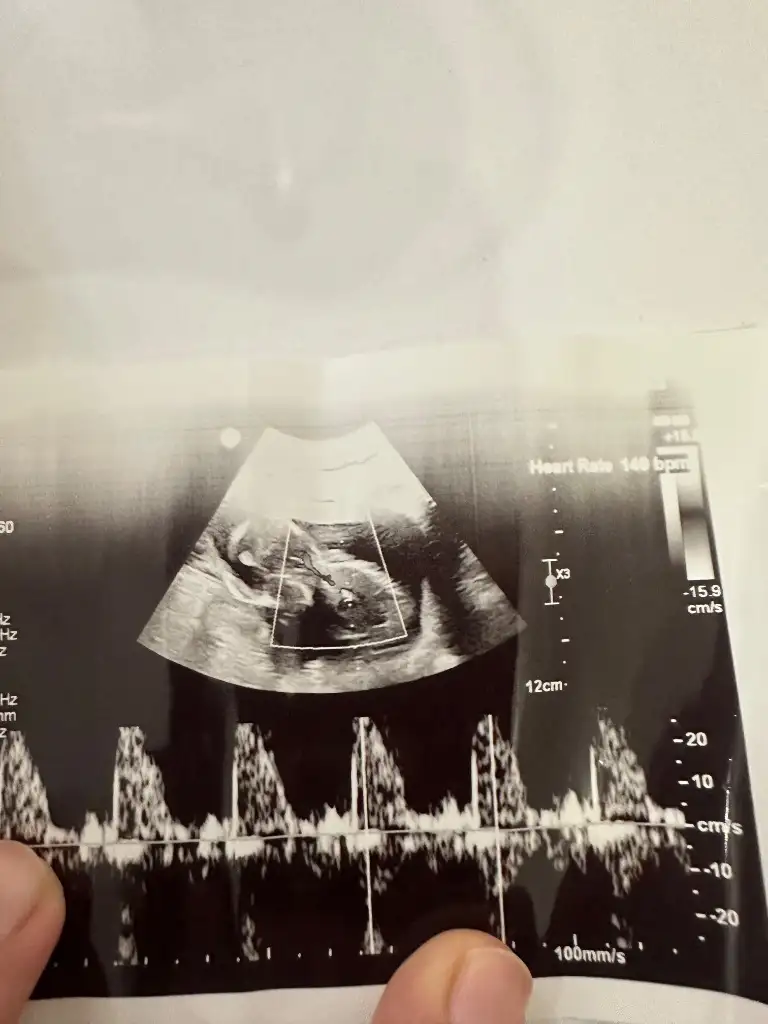

Bunada bakar mısınız rica edersemkız gibi

Bunada bakar mısınız

kızKızlar bana da bakar mısınız?? 13 haftalık

çok küçük ama kese kız gibiBana da yorum yapar mısınız 8 haftalık vajinal bakıldı